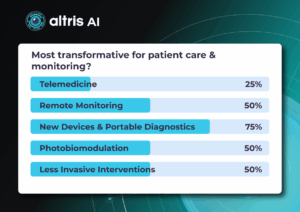

For this article, we surveyed eye care professionals on which optometry technology appears most promising to them. The answers were divided among AI for more precise diagnostics, advanced contact lenses, and new iterations of OCTs.

Of course, this is not the whole list of possible new tech in optometry, but these are the topics that draw the most attention today.

The article delves deeper into each of these technologies, as well as explores oculomics, the new way of understanding the correlation between eye pathology and overall human health.